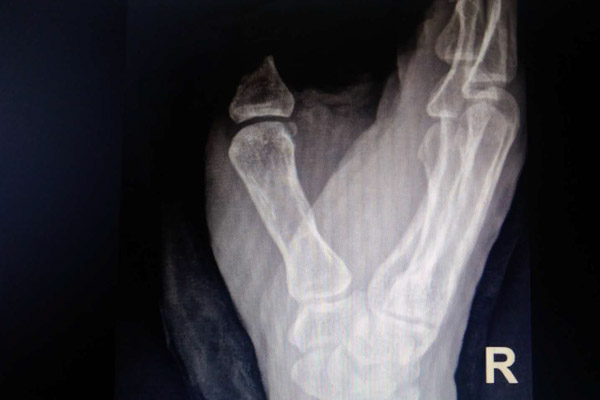

傷者工作中右手不幸被機(jī)器卷入,其右手拇指被卷入皮帶輪,導(dǎo)致右手拇指從第一掌指關(guān)節(jié)處完全離斷,近節(jié)指骨骨折,肌腱、血管、神經(jīng)完全撕脫抽出,并伴有大量出血,情況十分緊急。

為爭(zhēng)分奪秒保障手術(shù)最佳時(shí)機(jī),為患者進(jìn)行的斷指再植,手術(shù)分兩組同時(shí)進(jìn)行,急診科團(tuán)隊(duì)負(fù)責(zé)患者離斷拇指清創(chuàng),創(chuàng)傷骨科團(tuán)隊(duì)負(fù)責(zé)傷口清創(chuàng)修整,并為將要進(jìn)行吻合的血管、神經(jīng)、肌腱尋找新“供體”。

斷指再植成活的前提是建立有效的血運(yùn),吻合的動(dòng)脈、靜脈血管暢通?;颊吣粗讣‰?、神經(jīng)撕脫約30多厘米,動(dòng)脈、靜脈血管因撕脫傷同樣損傷嚴(yán)重,這對(duì)于創(chuàng)傷骨科醫(yī)療團(tuán)隊(duì)來(lái)說(shuō),是一項(xiàng)嚴(yán)峻的挑戰(zhàn)。為了保住傷者的拇指,創(chuàng)傷骨科醫(yī)療團(tuán)隊(duì)密切配合,骨折固定、肌腱神經(jīng)轉(zhuǎn)位、動(dòng)脈血管吻合一氣呵成,離斷拇指恢復(fù)正常血運(yùn);針線在顯微鏡下穿梭,患者拇指背側(cè)的靜脈血管全部完成吻合,三個(gè)半小時(shí)后,手術(shù)順利結(jié)束,患者被安全送回了病房。